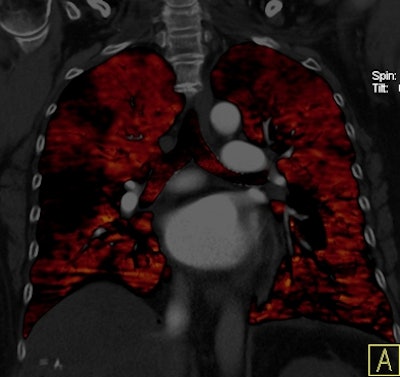

Dual-energy CT enables the selective display of iodine distribution within the pulmonary parenchyma following contrast-enhanced pulmonary CT angiography, which in turn permits the calculation of perfusion defect (PD) size in patients with suspected PE.

Depending on the shape and pattern of the defects at dual-energy CT, perfusion defects due to PE can generally be distinguished from, for example, patchy defects signaling other pathologies of the lung parenchyma, Bauer said.

The researchers measured perfusion defect size in the lung parenchyma caused by PE on dual-energy iodine distribution maps, and expressed it in two ways: as absolute quantification (VolPD in mL) and relative to the total lung volume (RelPD in %).

| Patient with bilateral segmental and subsegmental PE and large perfusion defects on dual-energy iodine distribution maps. All images courtesy of Dr. Ralf Bauer. |